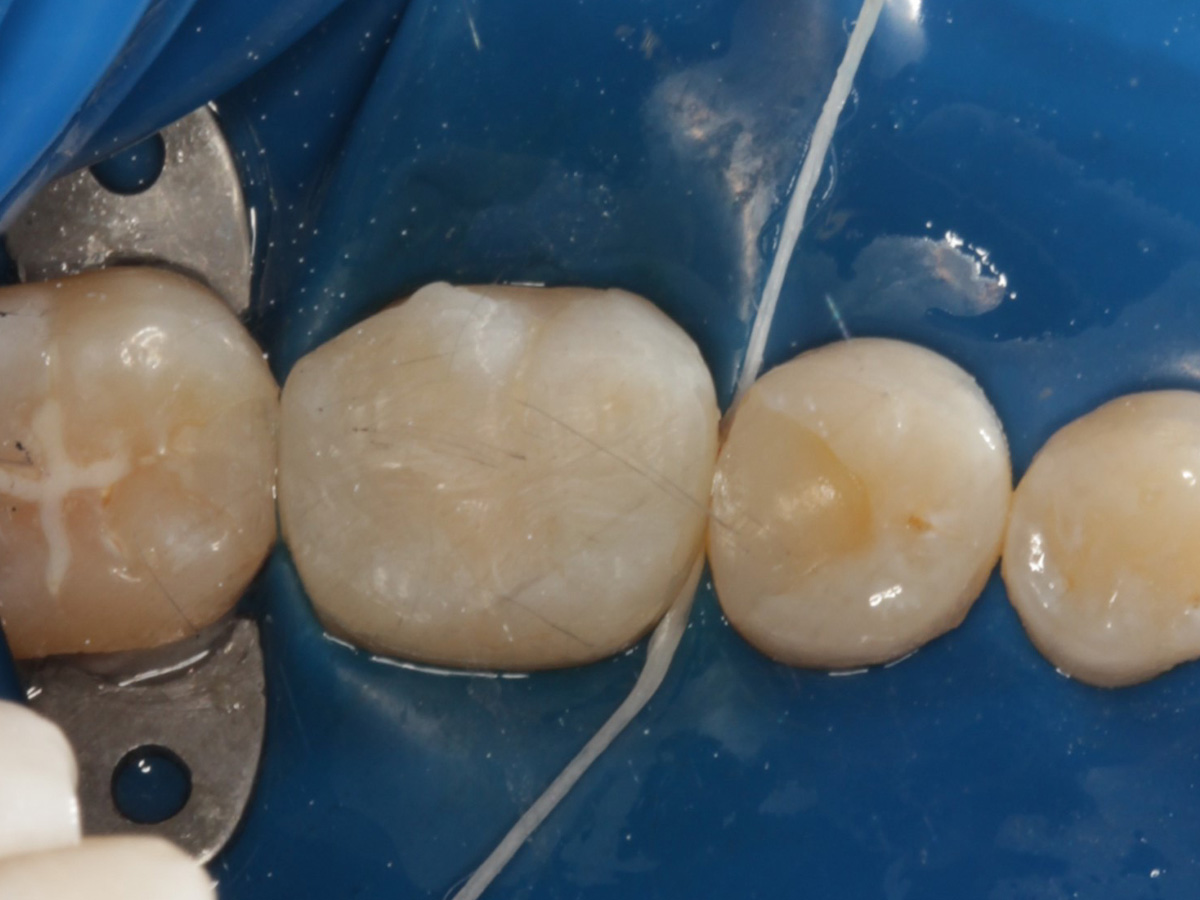

Abbildung 22

Fertige Restauration Zahn 46

Fazit

Also ich kann jetzt für mich sagen, dass die neuen Evolve Matritzen nochmal ein richtiger Schritt nach vorn hinsichtlich Formstabilität, Kantensteifigkeit, und aber insbesondere der Behandlung extrem tiefreichender (approximaler) Defekte sind. Obwohl diese Matrizen angeblich so dick sind wie die Biofit-Matrizen, sind sie gefühlt dünner und dabei gleichzeitig stabiler. Ein Riesenvorteil bei tiefer Zerstörung ist diese zusätzliche "Lasche", mit der fast alle Defekte sauber eingefasst werden können.